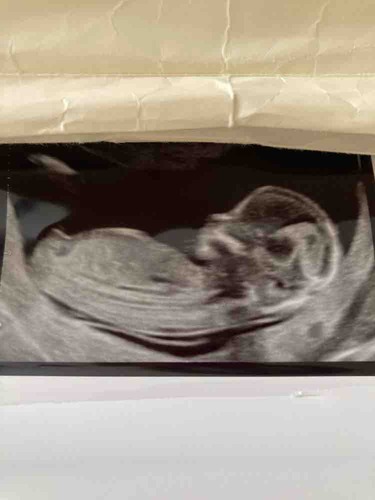

Jammergenoeg kan ik van de laatste echo ook de nub niet goed zien. En weet ook niet zeker of het de blaas is wat ik zie. Als je een filmpje hebt zou het mooi zijn als je een paar foto's maakt van stilstaand beeld. Maakt niet uit of het er meerdere zijn en of je toch wat van het beentje ziet zoals bij de vorige echo. Want soms lukt het met bewerken alles toch scherper en duidelijker te krijgen. Filmpjes kun je volgens mij nog steeds niet plaatsen in dit forum. Op het moment begin ik een beetje te neigen naar dat het een jongen in wording is. Maar moet daar toch wat meer dingen voor zien voor ik een gok neem.

Iemand die een gokje durft te wagen?🥰

Ik gok jongen in wording

Hoever ben je hier?

Blauw: omranding

Rood: Blaas

Groen: stand nub en blaas met ruggengraad

Zoals je kan zien in de ingezoomde echos met alleen blauw zie je een klein bolletje/boven de nub lijn. Dit is normaal het begin van de ontwikkeling van de pipi

De lijn van de nub veranderd dan in de balletjes.

Zoals op de echo met de andere kleuren lijnen is er meer schaduw bij gedaan waardoor je ook duidelijker ziet dat de nub omhoog staat. De blaas zit ook erg laag en van nub naar blaas naar ruggengraad staat het in een hoek naar de ruggengraad(📐) dit duidt op een jongen. Bij meisjes loopt het gelijk of bijna gelijk aan de ruggengraad(=) de blaas zit daar dichter tegen de nub aan en is de nub plat en is er geen bolletje.

Dus ik gok jongen

Bedankt voor de uitgebreide uitleg.👌🏻 Ik ben 13+6.

Moet wel zeggen dat ik wel wat meer had verwacht met dat termijn. Vaak zie je dan al echt pipi en balletjes omhoog staan. Maar kan ook liggen aan hoe ze de echo gemaakt hebben. Bij een meisje met dit termijn moest het zowiezo plat zijn. Dus denk dat ze expres de echo wat minder duidelijk(donkerder) hebben gehouden bij de nub heb ik wel wat vaker gemerkt.

Maar door alle duideljke dingen gok ik toch echt jongen. Laat je het nog even weten als je het weet?

Erg lastig. Vaak verwacht ik wat meer te zien maar lijkt of met de 13 weken echo ze expres de nub wat minder goed op beeld zetten. Op het moment gok ik toch jongen. Door het bolletje erboven en de blaas die lager ligt. Je had niet nog een echo?